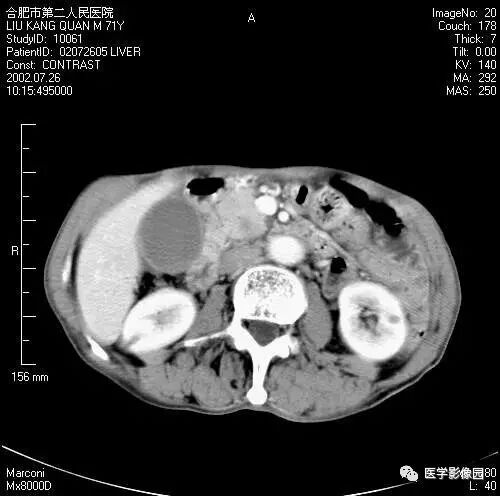

图6-4-20胰腺癌

A. 增强扫描见肝门部转移性淋巴肿(↑),

肝动脉部分被包绕(长↑),

可见大量腹水;

B.胰头部不规则分叶状增大,

胰体、尾部萎缩,

主胰管局限性扩张(↑),胆囊明显增大